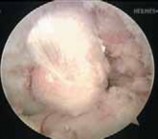

5. If the AL bundle is found to be intact, special care is taken to preserve this bundle while the overlying synovium and ruptured PCL fibers are débrided (

TECH FIG 5A

).

26. Fixation and closure are then performed. TECH FIG 5 • A. An intact AL bundle is preserved and the overlying synovium and ruptured PCL fibers are débrided. B. The exit point for the tibial tunnel along the sloped face of the posterior tibial fossa is just distal and lateral to the intact PCL insertion, as demonstrated by a long 18-gauge bent wire

A B loop.